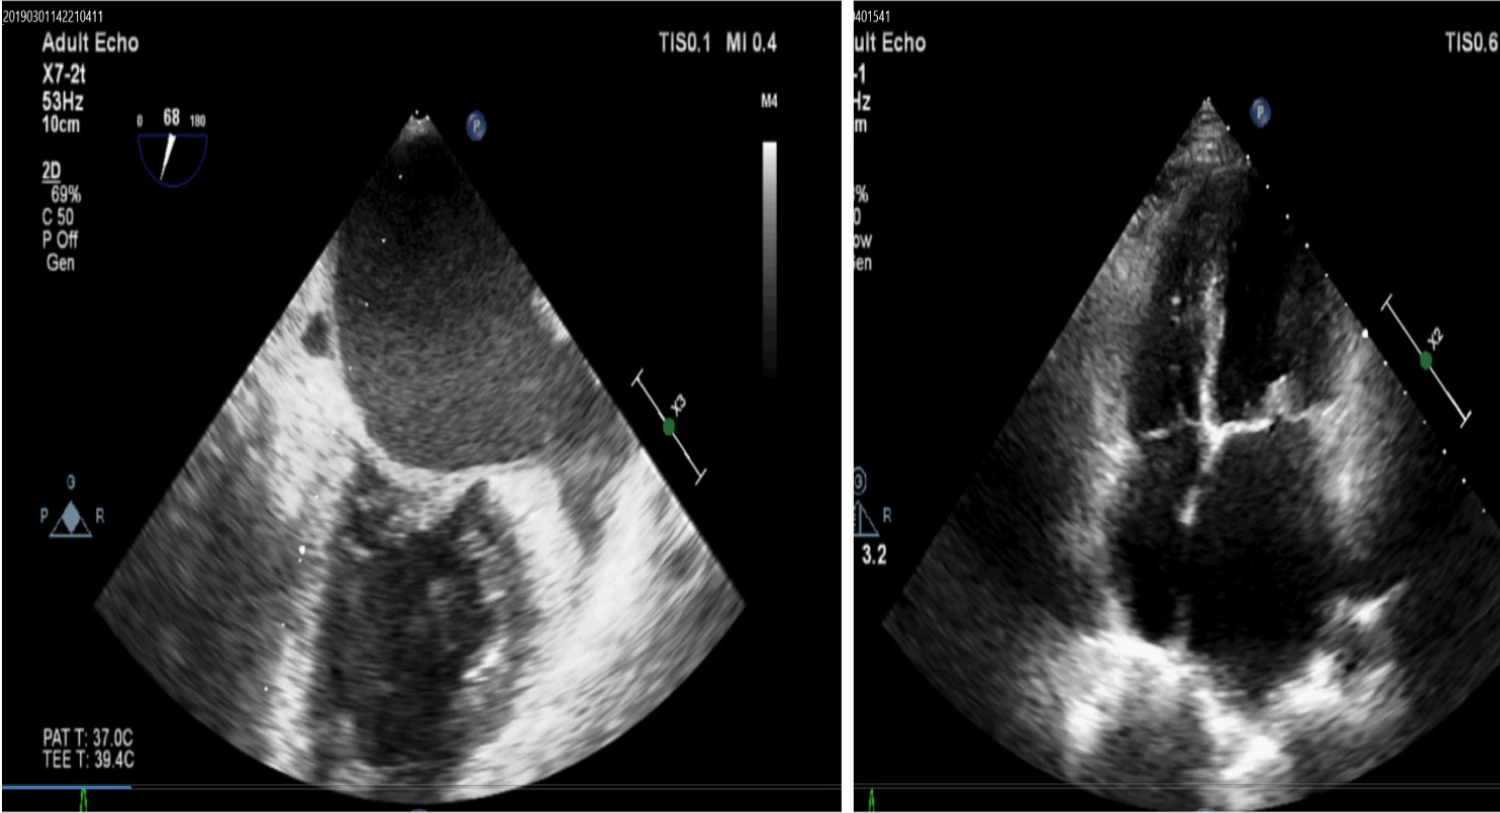

24-year-old male with very severe mitral stenosis of rheumatic etiology presented with one episode of transient left sided hemiparesis with full recovery within 24 hours. He was on optimum medical management that includes diuretics, beta blocker and digoxin. Her heart rate was 62/minutes and BP was 110/64 mm of Hg. She was also receiving injection benzathine penicillin once every three weeks. Transthoracic Echocardiography (TTE) was done which revealed thickened anterior and posterior mitral leaflet with restricted mobility. Mitral valvular area was 0.636 cm2 in 2D planimetry. Left atrium was dilated with measurements of 54 ml/m2 in volume. She was planned for PTMC (Percutaneous transluminal mitral commissurotomy) and TEE (transesophageal echocardiography) was planned for further evaluation. TEE revealed LA Spontaneous Echo Contrast (SEC) or smoke in the left atrium. It mandates initiation of oral anticoagulation in this patient. Coagulation profile was advised after initiation of oral warfarin therapy and titrations of doses were done to achieve proper INR value. Figure 1 demonstrating the LA smoke in swirling pattern in TEE (Left panel) and mitral stenosis in TTE in right panel. Video 1 showing the same in video format which is clearly showing the LA smoke of grade 2+ to 3+ intensity. Left Atrial (LA) appendage peak emptying flow velocity (LAAEV) was found to be 15 cm/s. This explains the occurrence of embolic manifestations in the patient. Therefore, TEE examination has a special role in such situations even when TTE is not showing any such abnormalities.

Figure 1: Showing the LA smoke in swirling pattern in TEE (Left panel) and mitral stenosis in TTE in right panel.